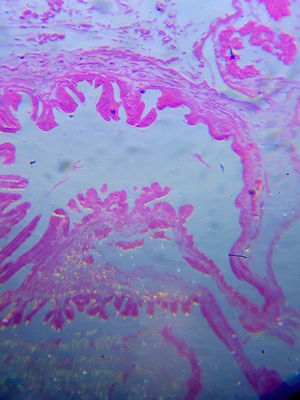

Lamina fiinita nervi motorii (End of motor nerve plate). Micropreparate on the optical glass

Lamina fiinita nervi motorii (End of motor nerve plate). Micropreparatus on the optical glass / Cyprus is narrow-leaf. Moscow region, macro objective, compact chamber (inversion)